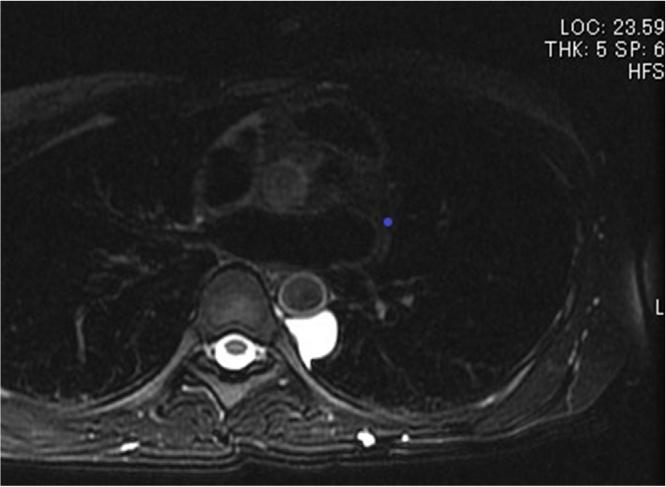

A 40-year-old woman was referred to our department for abnormal mediastinal tumor on computed tomography (CT). Chest CT revealed a 2-cm nodule in the left posterior mediastinum, while magnetic resonance imaging (MRI) T2-weighted scan revealed an elliptical, homogenous, and high-intensity neoplasm, and bronchogenic cyst or neurogenic tumor was suspected. She did not present with any symptoms. A thoracoscopic surgery was performed for the cyst removal. Histopathological examination revealed that the cyst wall was covered with a layer of columnar epithelium. Immunohistochemical staining revealed the presence of estrogen receptor (ER) and progesterone receptor (PgR). Therefore a diagnosis of mediastinal Müllerian cyst was made.

一名40岁女性因计算机断层扫描(CT)发现纵隔肿瘤异常转诊至我科。胸部CT显示左后纵隔有一个2厘米的结节,而磁共振成像(MRI)T2加权扫描显示为椭圆形、均匀、高强度的肿瘤,怀疑为支气管源性囊肿或神经源性肿瘤。她没有任何症状。为切除囊肿进行了胸腔镜手术。组织病理学检查显示囊肿壁覆盖有一层柱状上皮。免疫组织化学染色显示存在雌激素受体(ER)和孕激素受体(PgR)。因此诊断为纵隔苗勒管囊肿。